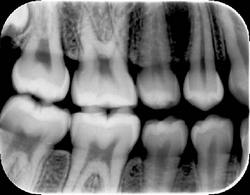

Finally, overall appearance of the image can be a very subjective assessment. Most dentists prefer image appearance and definition to be as much like conventional film as possible. The bitewing image in Figure 2 was taken with a CCD sensor and the bitewing image in Figure 3 was taken with a Soredex OpTime PSP sensor using a dry skull to maximize the definition of bone. Both images were made using the same kV, mA, and time, using the same enhancement features of the particular post-processing software utilized by the imaging system. From a purely subjective viewpoint, some dentists may prefer one image over the other depending on their personal likes and dislikes.